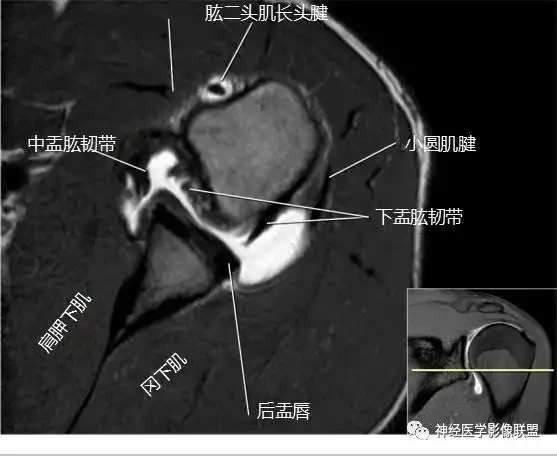

肩关节磁共振扫描规范及临床应用(一)

肩关节磁共振断层解剖

肩关节斜冠状面mr断层解剖_技巧

肩关节mri

肩关节磁共振(mri)解剖图_肩关节损伤_肩关节损伤介绍 - 好大夫在线